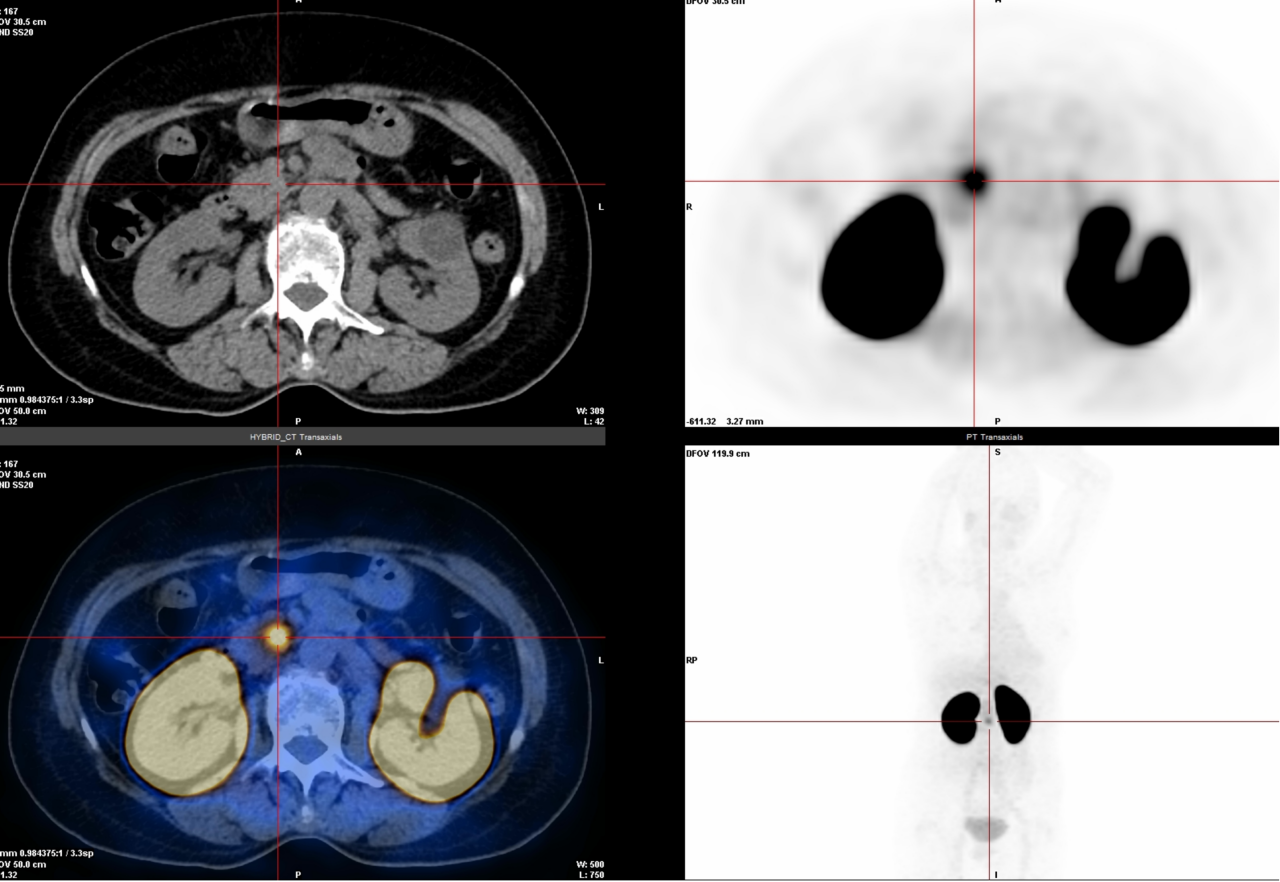

4. 醛固酮瘤、多发性骨髓瘤、惰性淋巴瘤检查(68Ga-Pentixafor):这些肿瘤表面有一种叫CXCR4的“标记物”,这种检查能精准锁定它。

△右侧肾上腺醛固酮瘤